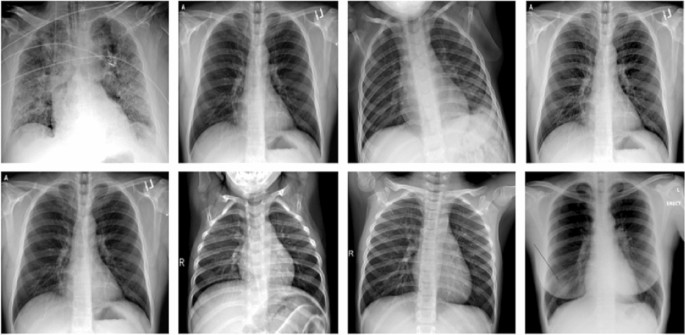

Dataset 2 is obtained form dataset (Mporas and Naronglerdrit 2020), Qatar University, and University of Dhaka (Chowdhury et al. 2020). The size of the dataset is \(|CXR\_Sample|=9300\). \(CXR\_Sample\) is divided into four subsets depending on the type of image as \(CXR\_Healthy\), \(CXR\_Tuberculosis\), \(CXR\_Pneumonia\), and \(CXR\_COVID\) each having size as 2400, 2350, 2375, and 2175, respectively. For multiclass classification, dataset 2 has been used. Figure 6 shows the sample image datasets 1 and 2.

Fig. 6

figure 6

A view of the multiclass classification dataset